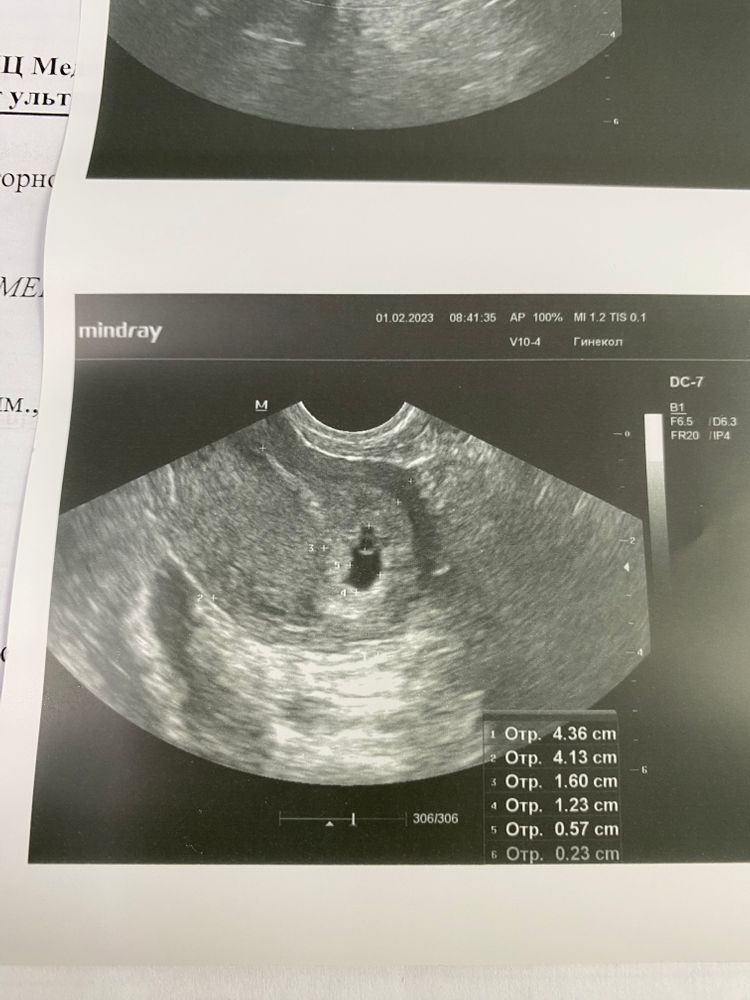

Ну что, мои дорогие мамочки! Вот наконец-то сходили вчера на долгожданный скрининг.Очень волновалась, так как неделю назад гинеколог напугала меня замершей беременностью, по маленьким размерам матки. Но узи показало, что все у нас прекрасно, Малыш уже подрос, во всю шевелиться. Не могли его толком поймать, чтобы сделать красивый снимок)

прикрепляю вам наше маленькая счастье с 5 недели, до сегодняшнего дня ❤️❤️